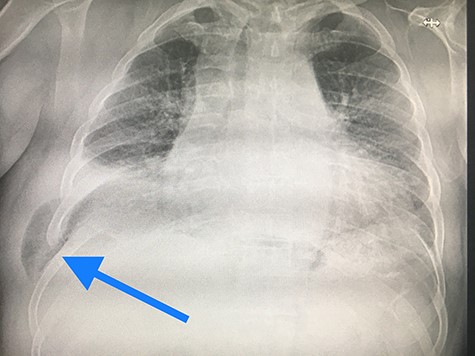

Physical examination revealed a localized movable soft tissue mass on the right side of the thorax. Chest radiography showed hazy airspace opacity, highly suspicious for lung herniation (Fig. 1).

Chest radiography showed hazy airspace opacity, highly suspicious for lung herniation.